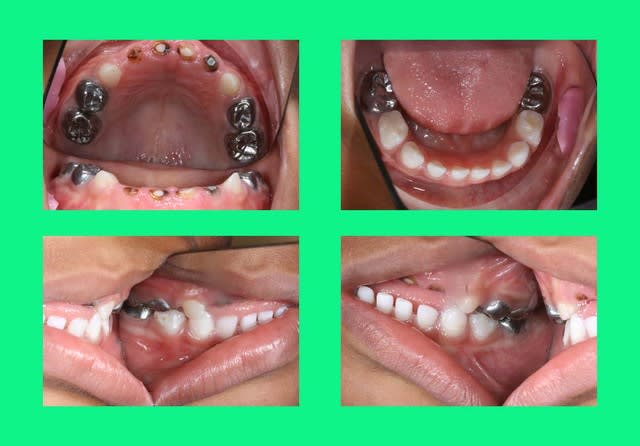

ds la mme,je récupère le frère

kelly:3 ans et 4 mois

Img 0965  small  ew2zyp - Eugenol

Img 0967  small  dahzlx - Eugenol

Enfin, comme on dit mieux vaut tard que jamais!! J'ai vu un petit comme ça en vac de pédo au centre de soins, 3 ans et demi, le père a laissé tomber au bout de 2 séances... C'est tellement égoïste je trouve de la part des parents de laisser leur gamin comme ça! Ceci dit je suppose que comme ça s'est bien passé avec antoine, ils vont faire la totalité des soins avec le petit, c'est déjà ça :)

Bon, vu la photo, je suppose que t'as des extractions et une petite prtohèse amovible prévues?

pr sig,les extractions st faites,les soins aussi,une couronne pedo est prévue en fevrier et la prothèse amovible pas faite: je n'ai pas de prothesiste pedo sur place et je ne suis pas persuadée qu'il va la porter